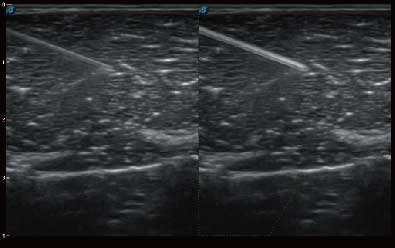

微米成像技术提升了对组织斑点噪声信号的抑制能力,并进一步强化边界信息,从而获得清晰图像。